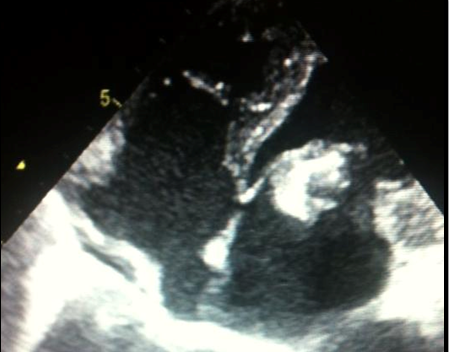

A 48 year old man, farmer originated from South West Tunisia, was first admitted in the nephrology department for acute renal failure in the context of prolonged fever, severe denutrition and loss of appetite. Laboratory exams revealed increased inflammatory biomarkers as well as severe anemia. Renal biopsy showed a non specific interstitial nephritis suggesting an infectious origin. Wright serology returned positive and patient history confirmed consumption of unpasteurized goat milk. Electrocardiogram showed sinus tachycardia and 2D trans thoracic echography 2D (TTE) found a large 25mm mass located in the atrial side of the anterior mitral valve suggesting a vegetation that has resulted in a severe mitral stenosis leading to pulmonary edema (Figure 1) (Figure 2). One day later, the patient developed an ischemic stroke in the right capsulo-lenticular brain area. He received high dose of antibiotics (Vibramycin, Rifampicin and Bactrim) and subsequently underwent a successful urgent surgery with mitral valve replacement number 21. Peroperative examination found a massive infection of the mitral valve with rupture of the anterior valvular chordae (Figure 3). Soon after surgery, renal function returned to normal, general status substantially improved. Antibiotics were maintained for 6 months with an unremarkable course during follow up. After discontinuation of antibiotics, the patient was kept only on oral anti vit K anticoagulant (VKA).

Figure 1 Two-dimensional echocardiography (Left parasternal view) showing large vegetation originated from the anterior mitral valve.

Figure 2 The same vegetation seen on four chamber apical view.